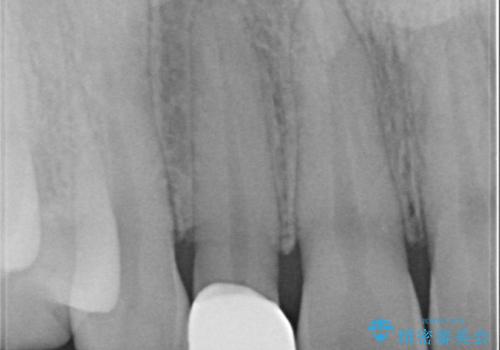

- 歯並びを矯正で整えたあと、上顎左右2番の歯(前歯の横の歯)の「矮小歯(歯が小さい状態)をオールセラミッククラウンで審美修復した症例です。

矯正によって歯並びはきれいに整いましたが、前歯全体のバランスをより自然で美しく仕上げるため、上顎左右2番にオールセラミッククラウンによる審美修復を行いました。

矮小歯はもともと歯が小さいため、削る量を最小限に抑えた負担の少ない治療が可能です。